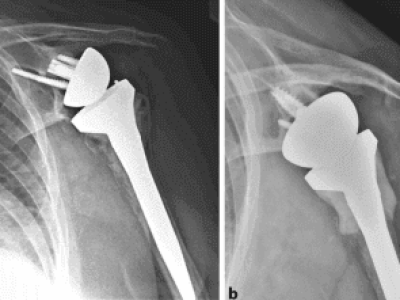

Overview: Periprosthetic humeral fractures occur around implanted hardware, such as after total shoulder arthroplasty (TSA) or reverse shoulder arthroplasty (RSA). Proper assessment and treatment depend on the stability of the implant and the fracture pattern. What are Periprosthetic Humeral Fractures?…